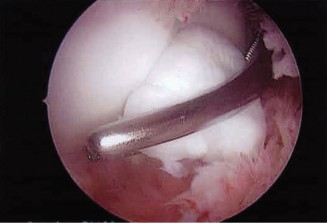

The patient undergoes conservative management consisting of rest, anti-inflammatory medications, and physical therapy. After six months, he is still not able to return to play and has progressively worsening symptoms with attempted throwing. He has a moderate elbow effusion as well as a 20-degree flexion contracture. An elbow MRI arthrogram is obtained and shown (Fig. 2–112). He elects to proceed with elbow arthroscopy. Intraoperative arthroscopic images are shown (Figs. 2–113 and 2–114).

Figure 2–114